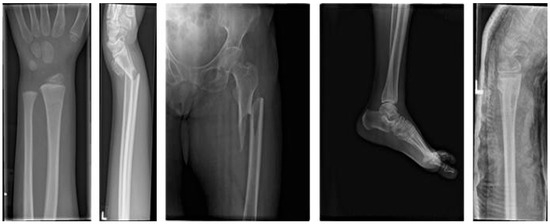

2.1. Acquisition of Medical X-Ray Fracture Images

- Abedeen, I.; Rahman, M.A.; Zohra Prottyasha, F.; Ahmed, T.; Chowdhury, T.M.; Shatabda, S. FracAtlas: A Dataset for Fracture Classification, Localization and Segmentation of Musculoskeletal Radiographs. Sci. Data 2023, 10, 521. Available online: https://figshare.com/articles/dataset/The_dataset/22363012/6 (accessed on 5 May 2025). [CrossRef]

- Nagy, E.; Janisch, M.; Hržić, F.; Sorantin, E.; Tschauner, S. A pediatric wrist trauma x-ray dataset (grazpedwri-dx) for machine learning. Sci. Data 2022, 9, 222. [Google Scholar] [CrossRef]

- Rodrigo, M. Bone Fracture Multi-Region X-Ray Data. Dataset. 2024. Available online: https://www.kaggle.com/datasets/bmadushanirodrigo/fracture-multi-region-x-ray-data/data (accessed on 5 May 2025).